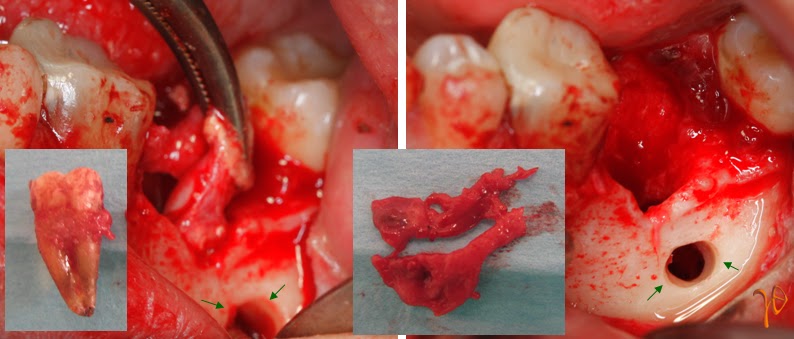

Ένας απλός χειρουργικός χειρισμός που μπορεί να διευκολύνει και να συμβάλλει σε μικρότερο τραυματισμό των ιστών, χωρίς να διακινδυνεύσουν η ριζικότητα της αφαίρεσης και ο έλεγχος του κάτω φατνιακού αγγειονευρώδους δεματίου, είναι η δημιουργία μικρού οστικού παραθύρου στο παρειακό τοίχωμα και η χρησιμοποίηση του για τη δίοδο εργαλείων σε συνδιασμό με τους διαφατνιακούς χειρισμούς στο μετεξακτικό φατνίο. Αν υπάρχει βοήθεια ενδοσκοπίου οι χειρισμοί μπορούν να γίνουν περισσότερο ατραυματικοί.

Εικόνα 2: Αφαιρείται ο # 37 και μετά από διάνοιξη μικρού παραθύρου στο παρειακό οστικό πέταλο (βέλη), εκπυρηνίζεται το κυστικό τοίχωμα (διανοιγμένο στην ένθετη φωτογραφία) με τη βοήθεια αποκολλητήρα, κοχλιαρίου και λαβίδας.